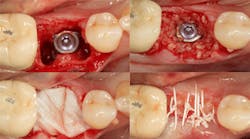

Excellent interseptal bone width was present, both buccal and lingual plates were present, and an adequate amount of bone was present coronal to the inferior alveolar nerve to allow for immediate implant placement. A sulcular incision was made around K and the adjacent teeth, and a full-thickness buccal and lingual flap was reflected. The tooth was sectioned in half, and the mesial and distal roots were elevated. The socket was degranulated with a round diamond bur and copiously irrigated with chlorhexidine gluconate 0.12% rinse. An osteotomy was completed in the interseptal area, and a bone-level 4.8- x 10-mm implant was placed to 35 Ncm. A mixture of cancellous and cortical allograft was infused with autogenous plasma-rich growth factor (PRGF), which was isolated during a preprocedural blood draw. The mixture was packed into the residual socket, slightly coronal to the implant platform to account for predictable resorption during healing. (13)

A 15- x 20-mm Ossix Plus membrane was hydrated in sterile saline for three minutes and trimmed to extend roughly 3 mm beyond the buccal and lingual extent of the bone graft and roughly 1 mm from the adjacent teeth. A sterile template is included in each membrane package; it can be trimmed to the appropriate dimensions and superimposed on the Ossix Plus membrane for final trimming to ensure the exact dimensions desired are obtained. This membrane can also be sutured, if necessary. When this technique is used, it is important to pass the suture needle through the membrane at a 90-degree angle to avoid tearing the membrane.

At this point, releasing incisions (vertical incisions and/or periosteal releasing incisions) can be made to achieve primary closure or to leave the membrane exposed and let the area heal by secondary intention. With the Ossix Plus membrane’s increased resistance to bacterial collagenase and the stresses of the oral environment, I feel comfortable leaving the membrane exposed and allowing the attached gingiva to heal over the membrane. This will result in reduced swelling and discomfort during healing, and there is less risk of damaging the mental nerve as it exits the mental foramen and fans laterally into the tissue. Attached gingiva around an implant will facilitate a more accurate impression, easier delivery of the restoration (and increased resistance to cement penetrating subgingivally), and easier hygiene for the patient. Also, when the implant is uncovered after healing, a tissue punch can be used, and there will generally be no need for a flap and sutures, thus improving the patient experience. Conversely, primary closure is imperative when performing a lateral or vertical ridge augmentation with or without simultaneous implant placement. Generally, when the extraction socket walls are intact, leaving the membrane exposed and allowing attached gingiva to grow over the membrane is predictable.

In this case, I placed an autogenous fibrin clot, which was isolated from the fractionated blood draw, over the Ossix Plus membrane and sutured, without obtaining primary closure, using a CV-5 Gore-Tex (W.L. Gore & Associates Inc.). This technique is designed to help facilitate the formation of a blood clot over the Ossix Plus membrane. It can be used with the addition of a collagen plug over the membrane, or you can just suture and allow a natural clot to form.